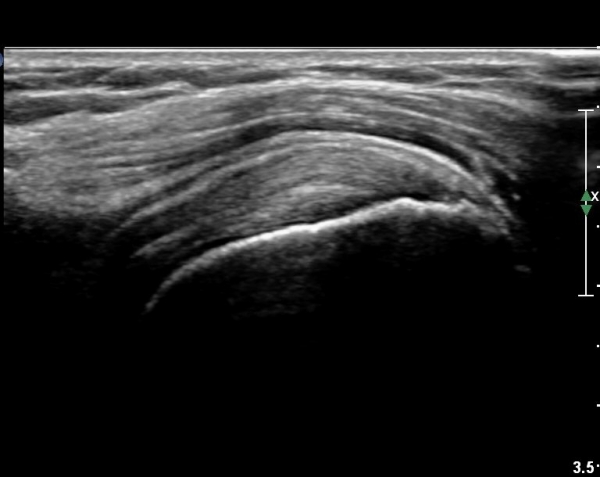

ȸÀü±Ù°³°£°Ý(rotator cuff interval) Ⱦ´Ü¸é°Ë»ç¿¡¼­ ÀÌµÎ¹Ú±Ù°Ç ¿ÜÃø¿¡ ±Ø»ó°ÇÀÌ °üÂûµÇÁö ¾Ê°í

´ë°áÀý Ç¥ÃþÀÇ »À°¡ ¿ïÅüºÒÅüÇÏ°Ô º¯ÇÏ¿´´Ù(±×¸² 1, 2)

ÀÌ´Â ½ÉÇÑ Ãæµ¹ÁõÈıºÀÇ °á°úÀ̰í ȸÀü±Ù°³ ÆÄ¿­À» °­·ÂÈ÷ ¾Ï½ÃÇÏ´Â ¼Ò°ßÀÌ´Ù.